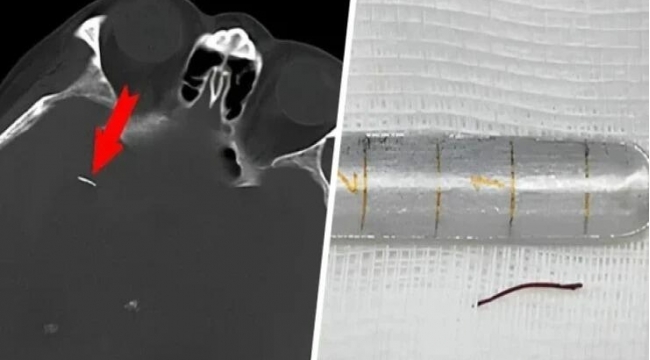

Beynindəki iynə ilə

20 İL YAŞADI